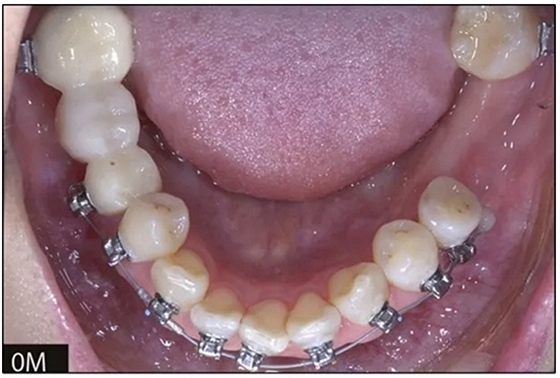

完全固定的Damon Q設(shè)備(加利福尼亞州Glendora的Ormco)與制造商指定的弓絲和附件一起使用。下頜弓,一開(kāi)始放入0.014英寸的鎳鈦弓絲,5個(gè)月后放入0.014×0.025英寸的鎳鈦弓絲。舌側(cè)扣和鏈圈放置在下頜尖牙和第二前磨牙上以控制扭轉(zhuǎn)。在治療的第7個(gè)月,將下頜弓絲換成0.017× 0.025英寸的β鈦絲。另一個(gè)舌側(cè)扣和鏈圈放置在下頜左側(cè)第三磨牙上以提供近中牽引力(圖9)。在16個(gè)月的治療結(jié)束時(shí),所有的扭轉(zhuǎn)都得到了矯正,缺牙間隙縮小到8 mm(圖8),但由于頰側(cè)骨板的嚴(yán)重吸收,牙槽嵴的寬度仍然很窄(約3 mm)(圖9)。通過(guò)正畸移動(dòng)下頜左側(cè)第二前磨牙,在前磨牙之間產(chǎn)生一個(gè)種植部位。在第一和第二前磨牙之間的弓絲上放置一個(gè)推簧,并將舌側(cè)扣和鏈圈放置在第一前磨牙和第三磨牙之間(圖9),在頰側(cè)和舌側(cè)施加力。施力均為輕力,每個(gè)表面上約2盎司(28.3 cN)以控制牙根側(cè)面的吸收。

圖8

圖9